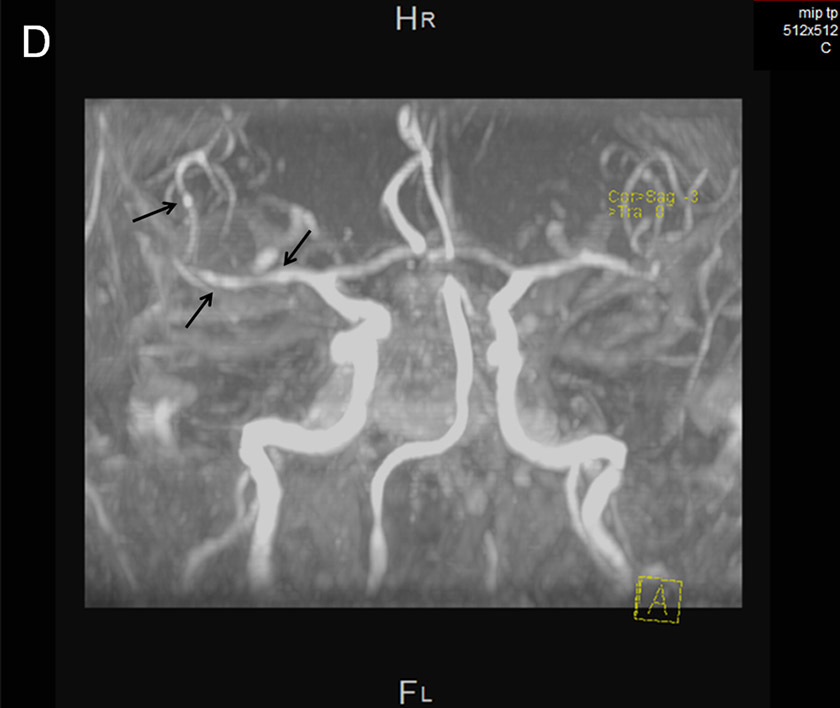

Cerebral MRI.

D MR angiography: Arrows highlight arterial irregularities suggestive of vasculitis.

Two days later the patient became drowsy again with signs of upper brainstem dysfunction. Cerebral MRI showed meningeal enhancement and widespread punctate ischaemic-type lesions affecting vascular beds of both carotid and vertebral arteries bilaterally (fig. 1 A–C). MR angiography showed numerous irregularities of the distal arteries, suggestive of vasculitis (fig. 1D). Antibiotic treatment was broadened to include meropenem 3 × 2 g and dexamethasone was restarted but brainstem dysfunction did not improve. Supportive treatment was withdrawn and the patient died on day 21 post-surgery. Subsequent CSF cultures were sterile.